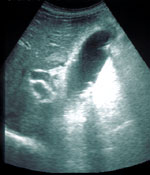

La Ecoendoscopia o Ultrasonografía Endoscópica integra en una misma exploración el estudio ecográfico y endoscópico. Se realizará siempre en ayunas y con sedación optativa. Para la Ecografía Endorectal bastará un enema de 250 cc, una hora antes de la exploración.Existen varios tipos de Ecoendoscopia dependiendo del órgano a explorar (Esofágica, gástrica, biliar, etc..). Las indicaciones son fundamentalmente la estadificación del cáncer digestivo y el estudio de las lesiones submucosas. Las Minisondas serían imprescindibles cuándo exista una estenosis maligna en el tubo digestivo, y cuando interese introducirlas por la papila para estudiar la via biliar. El Doppler se utilizará para el estudio de la hipertensión portal.

* En la imagen se puede observar (abajo) nítidamente las cinco capas del estómago